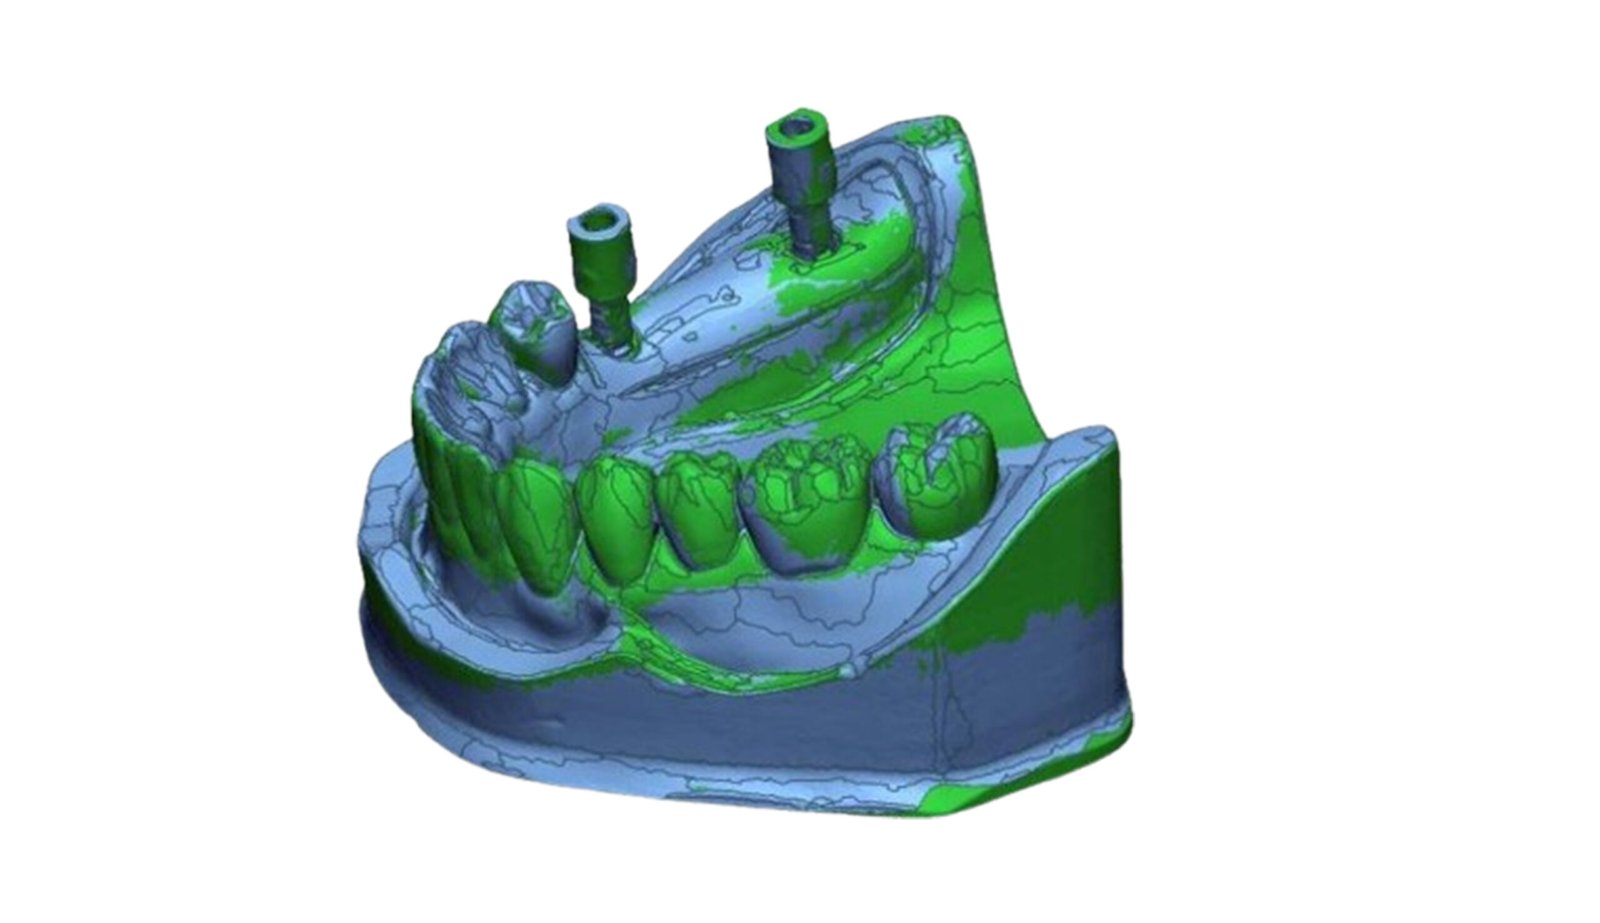

This section specializes in high-precision 3D deviation mapping to compare pre- and post-treatment anatomical or implant-related geometries. Using advanced superimposition and deviation algorithms, we quantify micro-level shifts, deformation zones, and structural discrepancies with sub-millimeter accuracy. These analyses support quality control, surgical verification, and design validation. The resulting deviation heat-maps provide clear, data-driven insights that enhance clinical decision-making and device optimization.